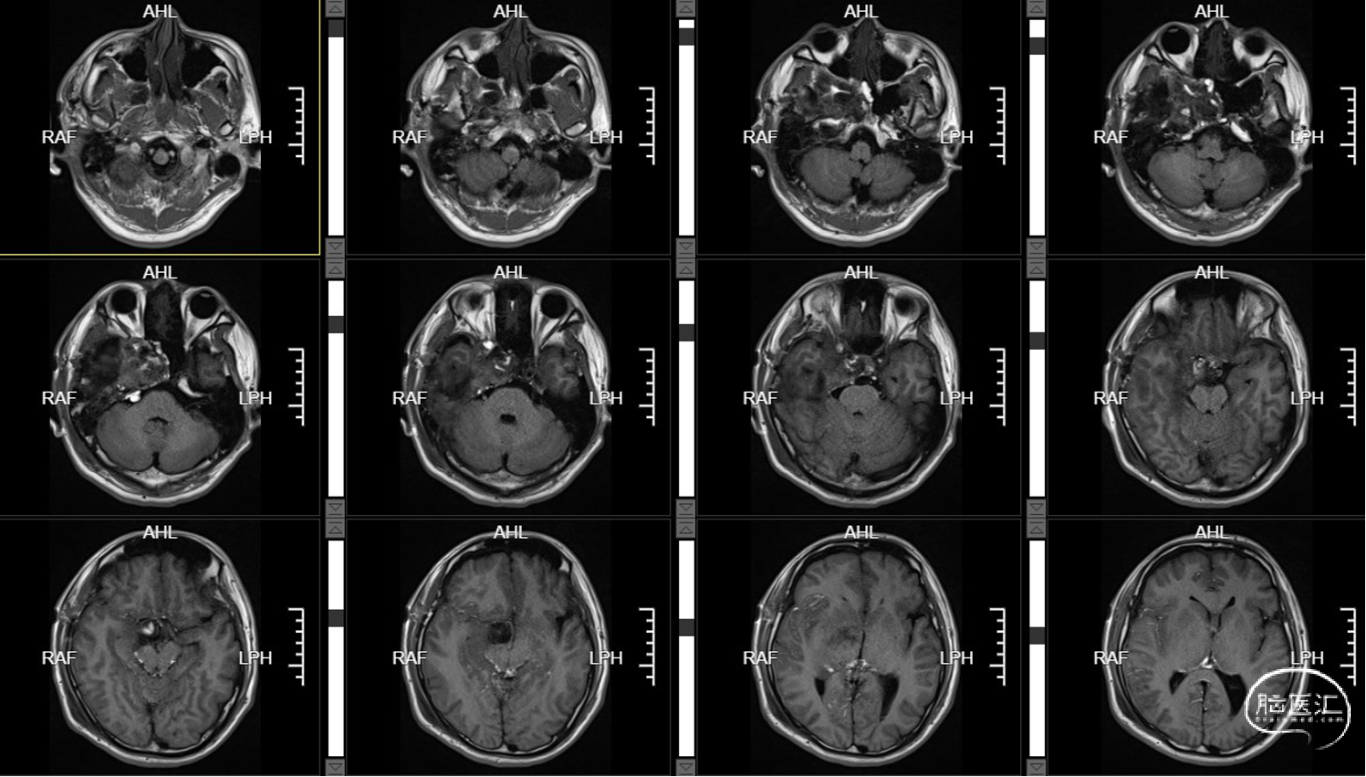

术前T1+C